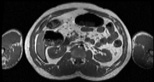

Visible Human male: Sectio transversalis 1613

CT

NMR

Pd                          / T2 \                         T1